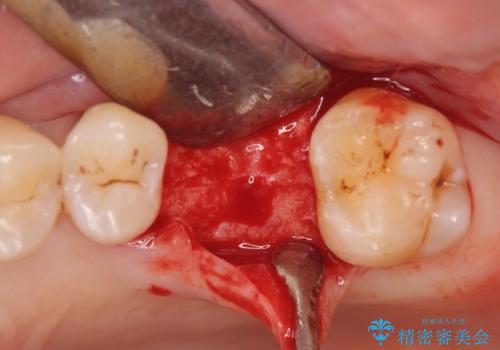

歯が割れるほどの咬合力が強い方でしたので、3本の歯を2本で支えるブリッジではなく、咬合負担能力の増えるインプラント治療にメリットが大きいと言えます。

- 外科手術のため、術後に痛みや腫れ、違和感を伴います